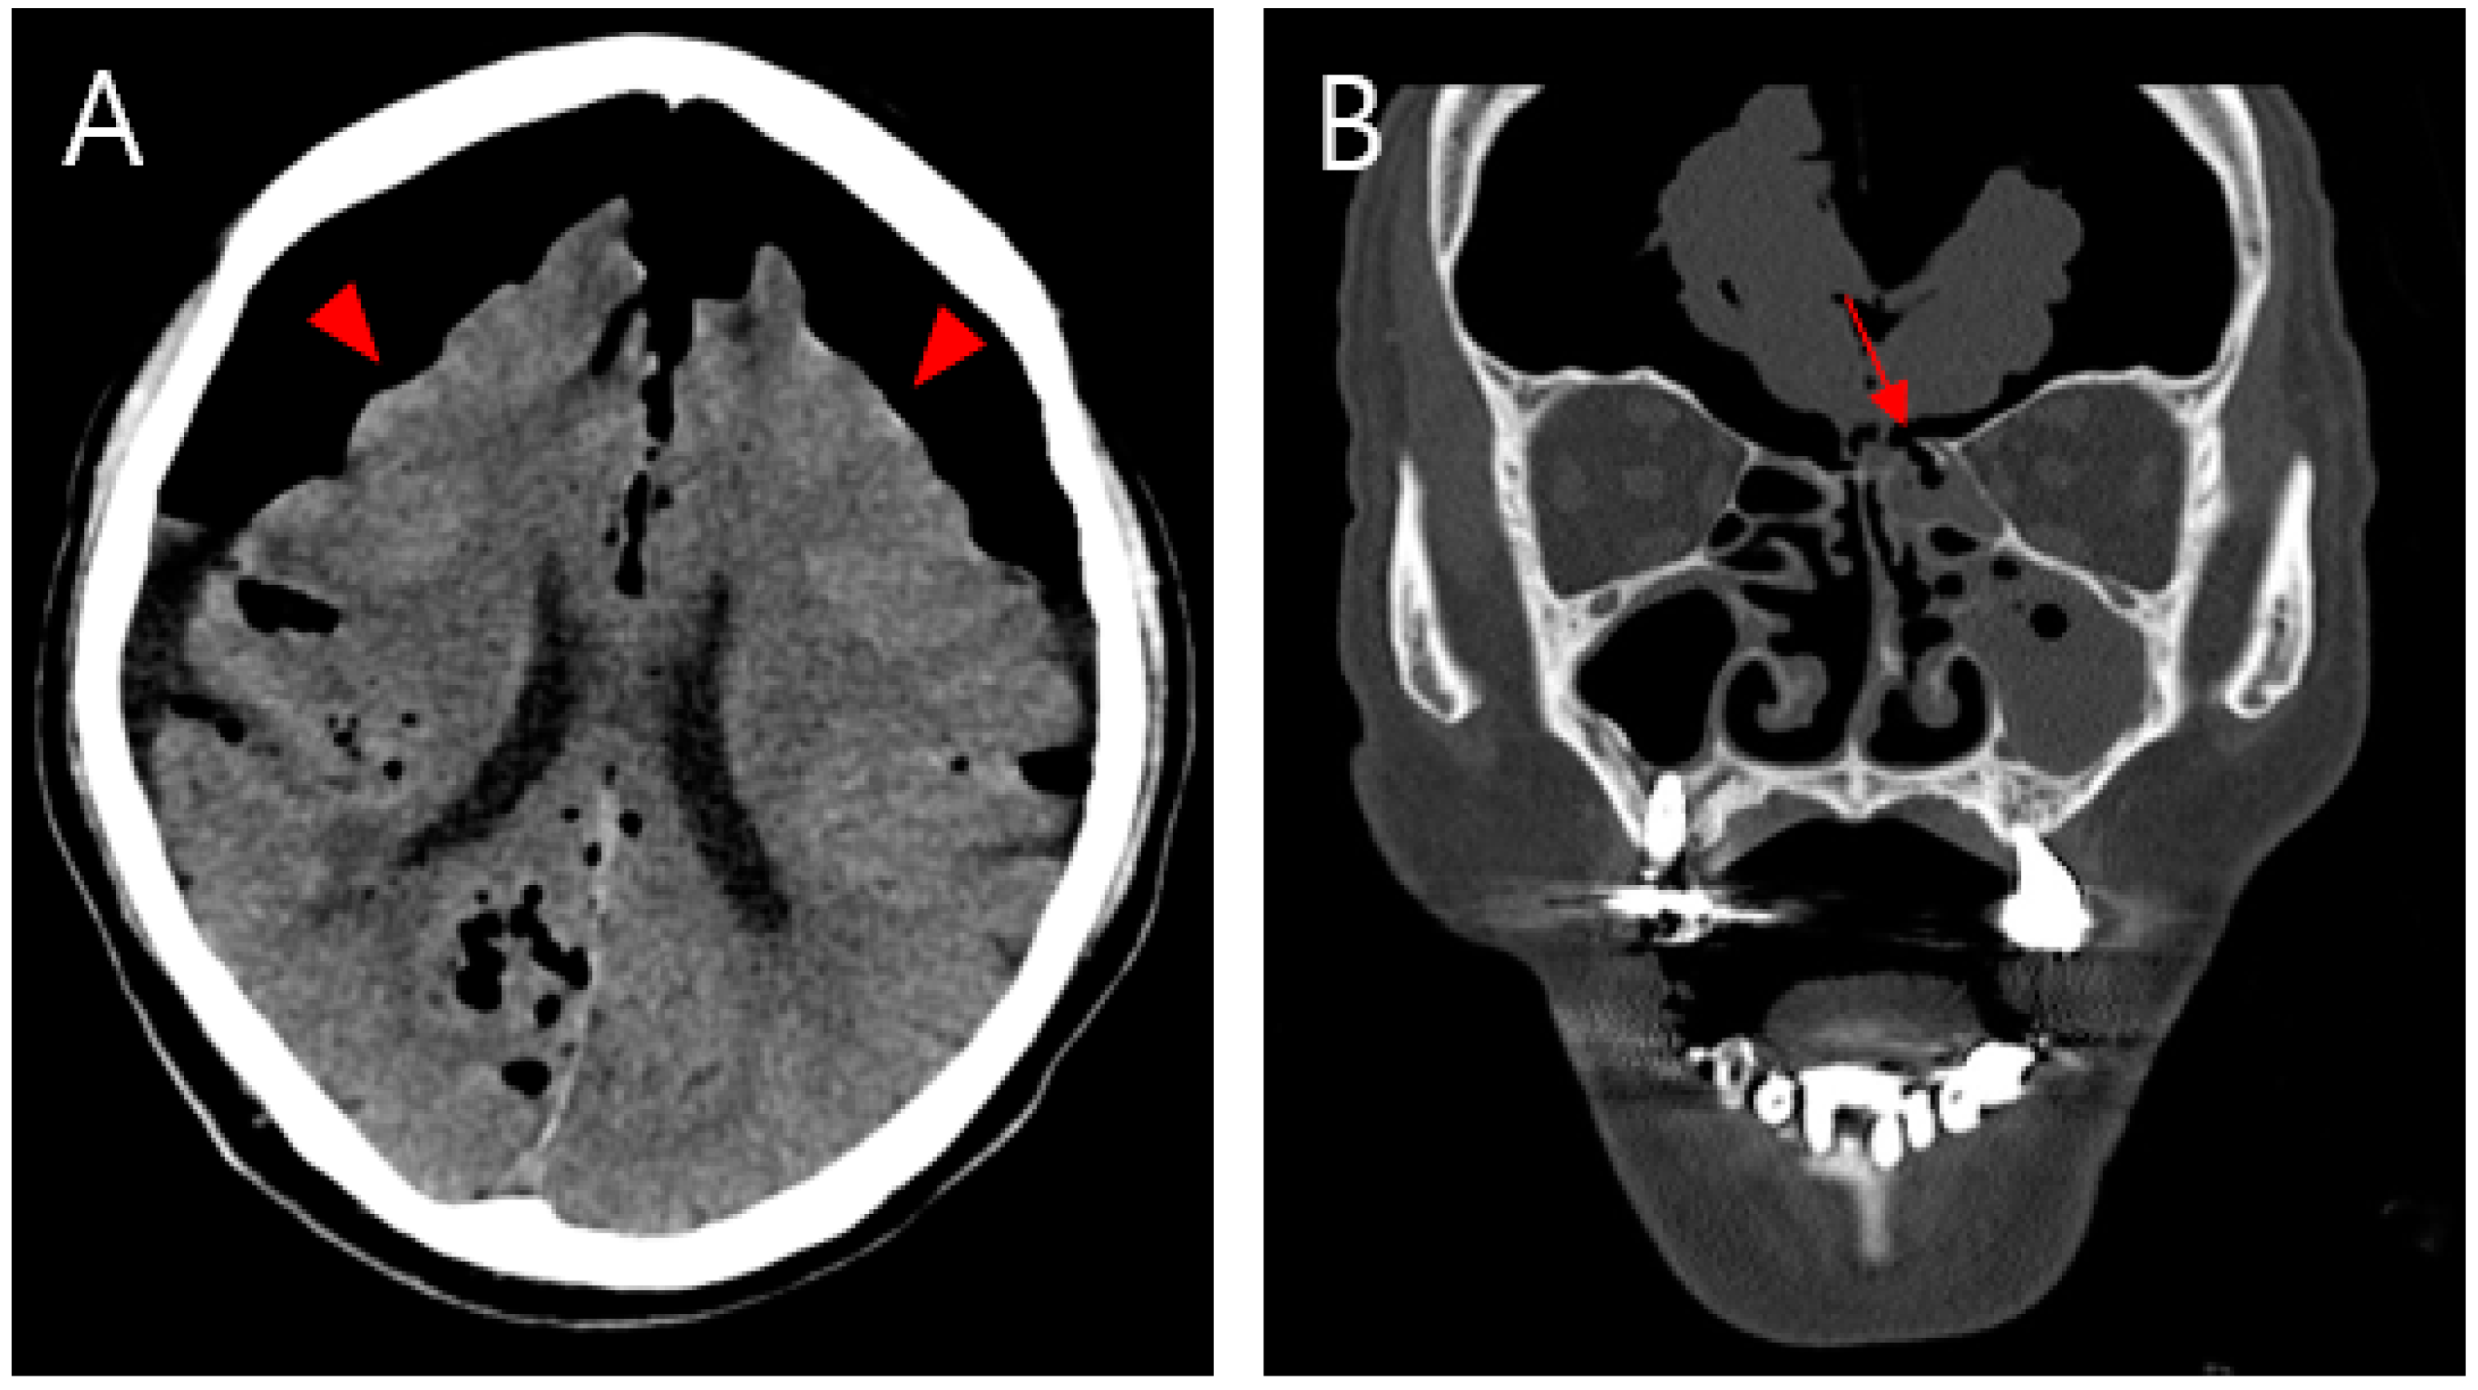

(A) Non-contrasting brain CT image showing pneumocephalus between the tips of the frontal lobes and the interhemispheric fissure, causing brain compression and demonstrating the Mount Fuji sign (arrowhead). (B) CT image of the paranasal sinus shows a fracture of the left ethmoidal roof (arrow). An 81-year-old male patient was admitted to our emergency room (ER) with mental cloudiness. Three hours prior to admission, he had slipped and tripped over a branch, injuring his nose. His initial Glasgow Coma Scale (GCS) was 11 (eye, 2; verbal, 3; motor, 6) and he had dyspnea upon arrival at the ER. Despite the high-pressure oxygen mask therapy, the continuous increase in oxygen demand required intubation and ventilator support. A physical examination revealed swelling, redness and bruising around his nose and a large amount of bloody rhinorrhea. A neurological examination revealed no specific findings other than decreased consciousness with mildly increased markers of infection in the laboratory examination. Computed tomography (CT) of the brain showed extensive pneumocephalus with brain compression, described as the Mount Fuji sign, and a CT of the paranasal sinus revealed a fracture of the left ethmoidal roof (Figure 1). A chest CT for evaluating lung problems revealed pneumonia in both lungs. With the diagnosis of tension pneumocephalus induced by an ethmoidal roof fracture, we performed combined surgery with an otolaryngologist. Through an endoscopic approach, cerebrospinal fluid (CSF) leakage was observed at the horizontal (cribriform) plate of the ethmoid area with a bone defect (6 mm). Closure of the dural and bone defects was performed using a bone graft, a mucosal flap, and fibrin sealant (Evicel) (Figure 2). After reconstruction of the ethmoidal roof, Burr hole trephination in the right frontal area was carried out with normal saline irrigation (Figure 3A). However, craniotomy was performed to remove the persistent intracranial air that caused brain compression because of aggravation of the neurological symptoms and no improvement in brain imaging. According to the post-operative CT, the pressure on the brain was reduced by removing the air, which thus improved the pneumocephalus (Figure 3B). After admission to the intensive care unit (ICU), postoperative conservative treatment was applied, including bed rest, supplemental oxygen therapy, and empirical antibiotic treatment for meningitis; central nervous system (CNS) infection was suggested by an analysis of the CSF. The patient gradually improved over a period of three weeks of hospitalization, as did the pneumonia, after which he breathed well without oxygen supplementation. At the time of discharge, his GCS score was 15, which was an improvement compared with the first time. At the one-month follow-up visit, the patient had no neurologic symptoms, and there were no specific findings revealed by brain CT and nasal endoscopy (Figure 4). Pneumocephalus is defined as the presence of air or gas in the intracranial cavity. The most common cause is head trauma; other reasons include neurosurgeries and spontaneous occurrences caused by tumors in the base of the skull, other tumors, infections, and barotrauma [1,2,3,4]. There is still much controversy about the mechanism; however, the most common theory can be explained by Horowitz’s “inverted soda bottle effect”. As a result of physiological drainage during straining, coughing, sneezing, the Valsalva maneuver, or iatrogenic lumbar drainage, excess loss of CSF leads to negative pressure in the cranial cavity [5,6]. Likewise, our case can be explained as massive CSF leakage due to an ethmoidal roof fracture, which trapped air through intracranial pressure. Pneumocephalus can be classified into two types: simple and tension. Patients with simple pneumocephalus are mostly asymptomatic. Sometimes, it can cause headaches, confusion, nausea, vomiting, and focal neurological symptoms. In most cases, conservative treatment, such as supplemental oxygen therapy [7], is required. However, in cases of tension pneumocephalus, which can cause brain compression and midline shifting to severe neurological symptoms, active management such as surgical decompression is required, and treating the primary cause is essential [8]. In this case, even though ethmoidal roof repair and burr-hole trephination were performed in light of the diagnosis of tension pneumocephalus with an ethmoidal roof fracture, craniotomy was carried out because of the persistent neurological symptoms after the operation. The patient showed an improvement in his symptoms after the operation. As tension pneumocephalus can cause severe neurological symptoms, rapid diagnosis and aggressive treatment should also be required by considering craniotomy.